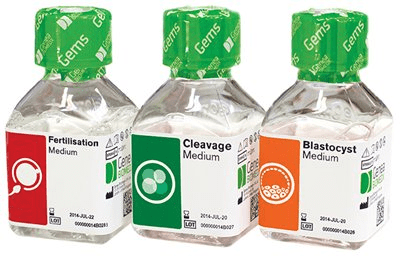

Genea vyvinula a stále vyvíjí vlastní kultivační média, která se v současné době používají ve více než 600 klinikách po celém světě. Genea brzy představí už 3. generaci kultivačních médií. Jakmile tato média splní podmínky pro certifikaci, začneme je používat v naší laboratoři.